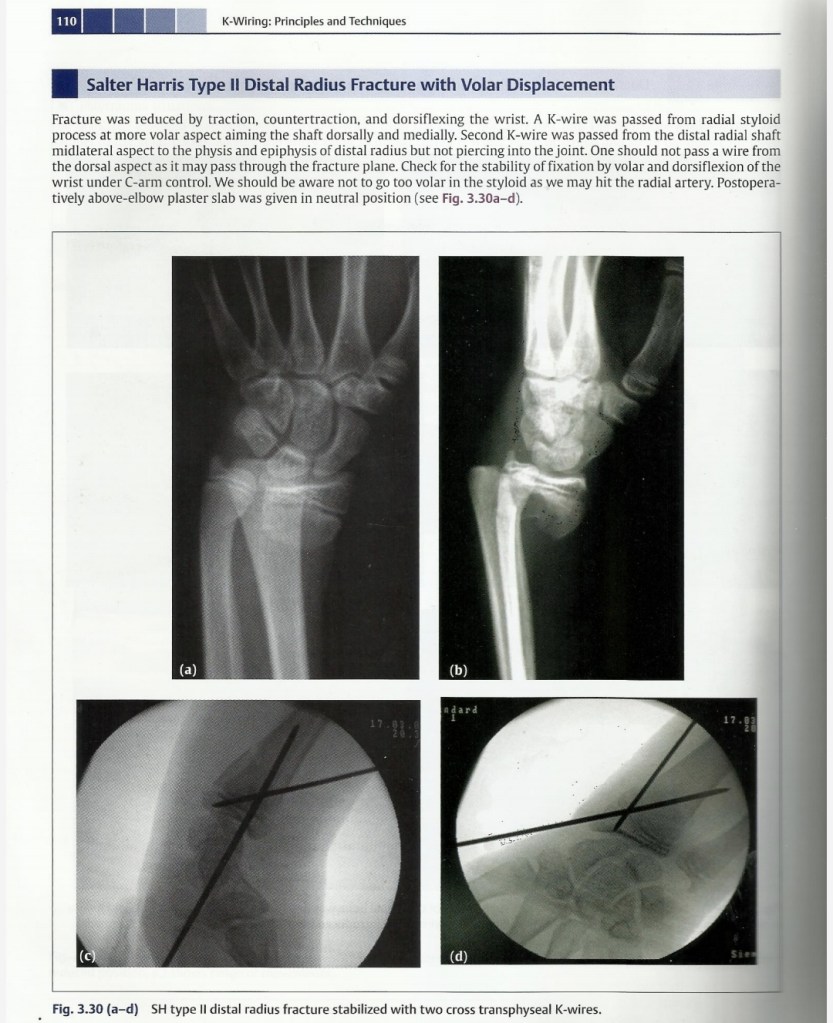

Lecture Pediatric Orthopedic injuries